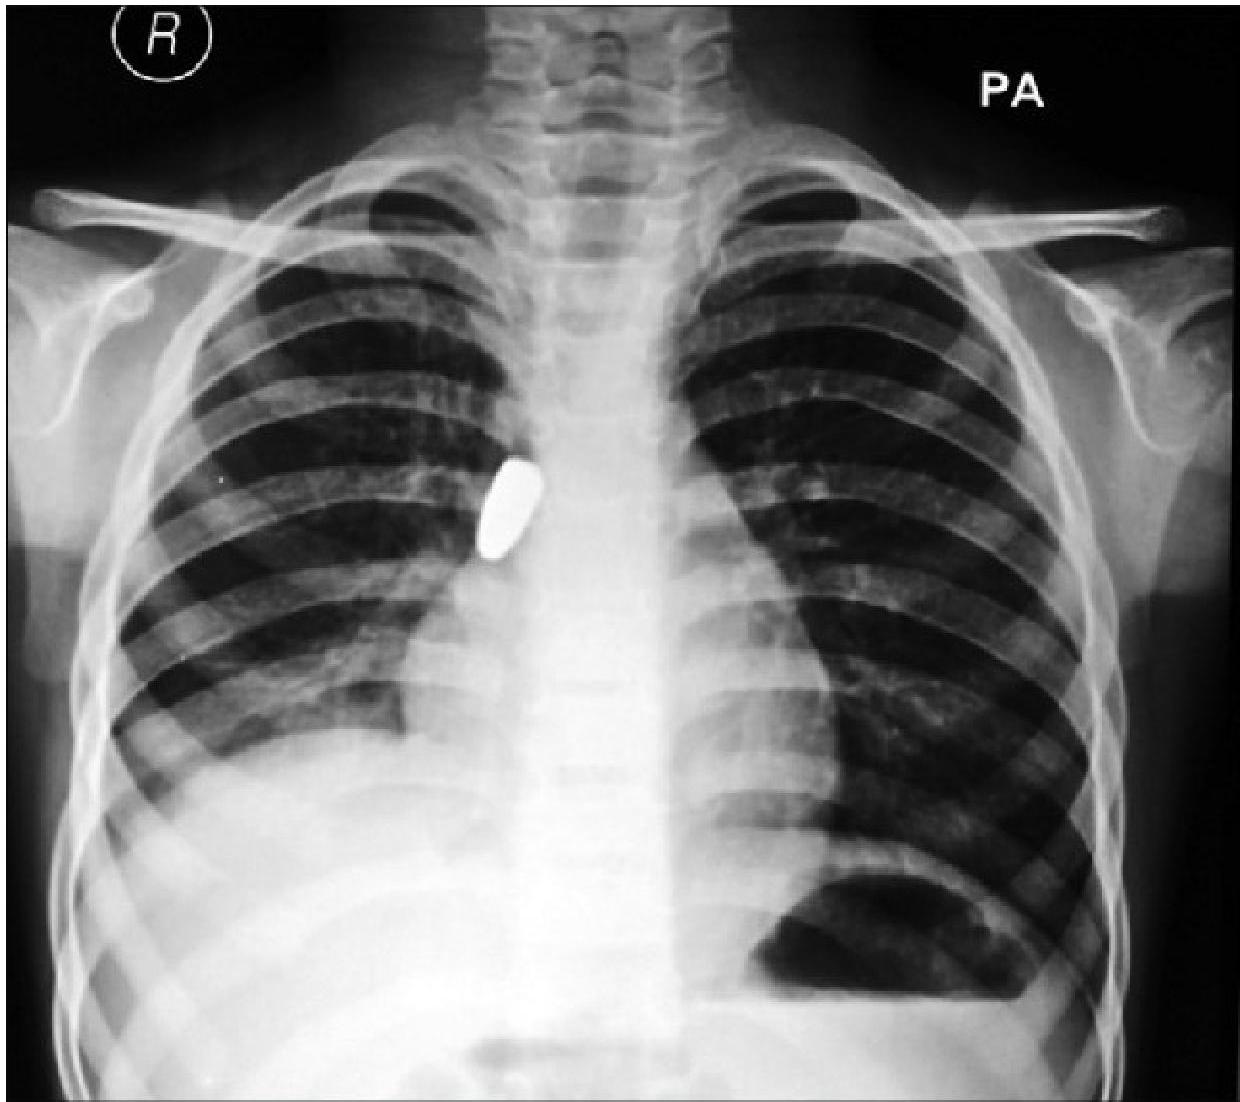

- 10% of FBs are radiopaque.

- Bronchial FBA Findings in chest x-ray:

- Hyperinflated lung

- Atelectasis

- Mediastinal shift

- Pneumonia

Left: Focal pneumonia in lower right lung lobe due to aspiration and airway obstruction. Right: Coin in the esophagus.

Foreign body aspiration of a coin in the esophagus